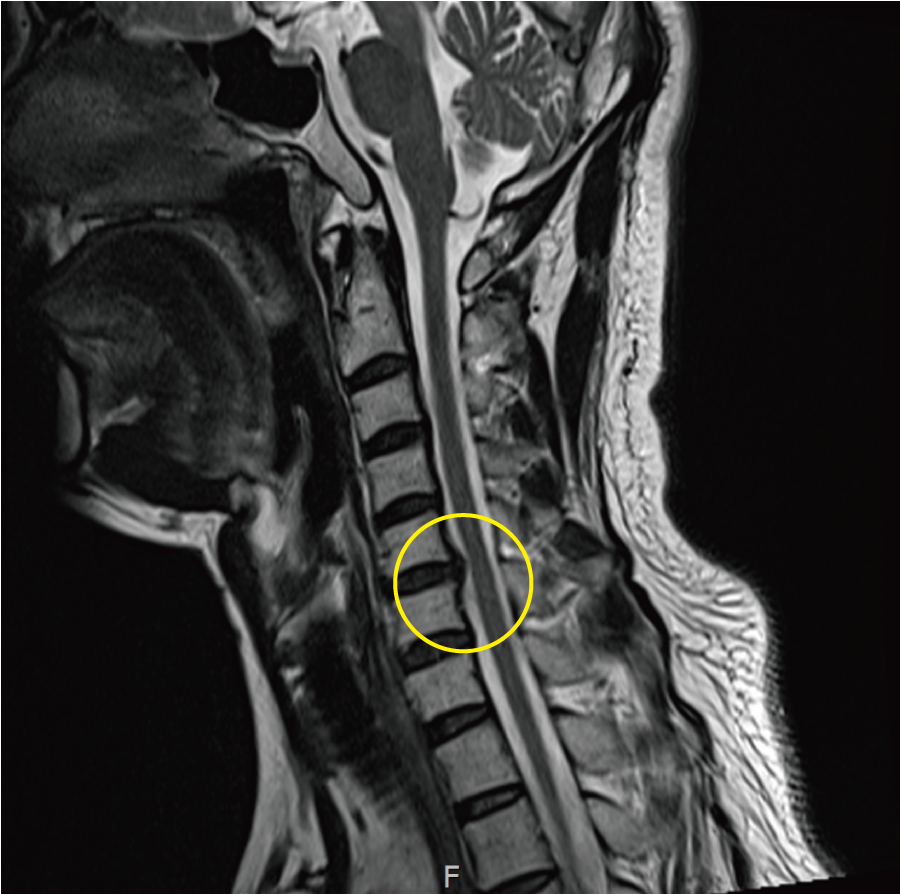

목 디스크 증상 총 정리 중 원인이고요. 한방 의학정보에 의하면 목 디스크는 목 뼈 사이 추간판이 파열됐거나 탈출되어 경추 신경의 자극, 압박으로 인하여 목, 어깨, 등, 팔 등 통증과 신경학적 증상이 있는 질환이예요.

경추는 제일 위쪽 목에 있는 7개의 뼈이라고 합니다. 경추는 운동성이 크므로 경추의 추간판은 압력에 의해 탈출되어 척수, 신경근을 억압되게 된다 하였습니다.

목 디스크는 여러 차례의 뼈에서 문제가 생겼느냐에 따라 증상이 다르죠. 어찌 경우에는 어깨와 팔이 도대체 아프지 않을 수 있으며 어떠한 경우에는 어깨, 팔, 손가락 등 모두 아플 수 있다고 합니다.

목 디스크는 탈출된 정도, 방향에 따라 증상이 모두 차이나기 때문에 특징적인 증상에 대해서 둘러보겠습니다.